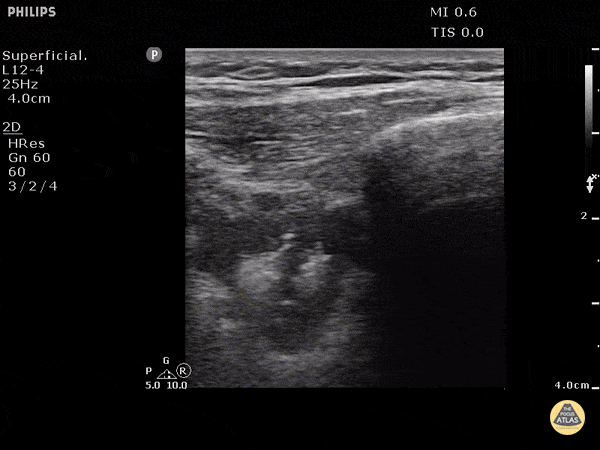

Pulmonary - Pulmonary Embolism (B mode)

PE with linear probe in B mode. Pulmonary embolism can be seen by disruption of the pleural line. 0.5cm to 3cm disruptions are typical for PE. Doing DVT studies and echo can help strengthen your diagnosis. Dr. Justin Bowra et al.